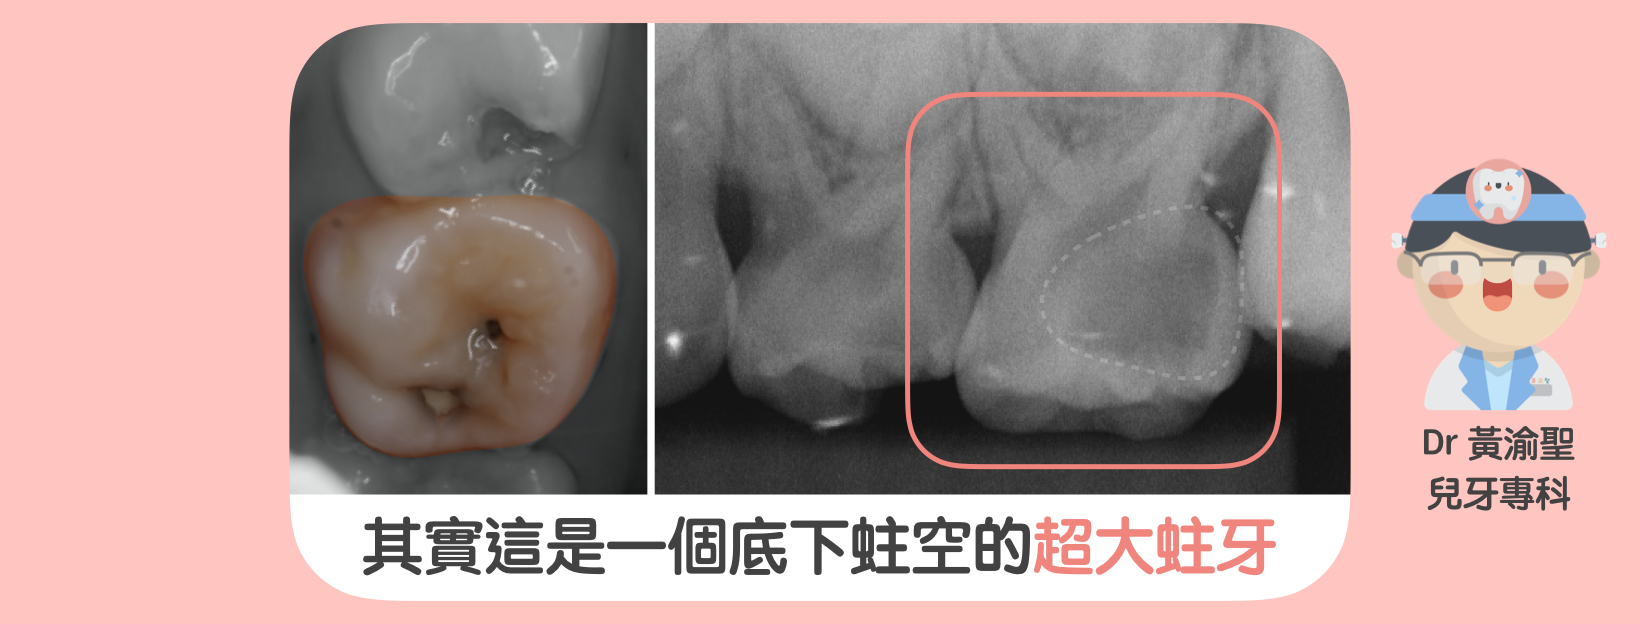

0 評論 0 FacebookTwitterTelegramLINEEmail 為什麼醫生總是要求小朋友拍X光片呢 拍攝X光是非常重要的啦 牙科X光就好像牙科醫師的照妖鏡 可以讓口腔狀況無所遁形 為了治療的精確性 請盡可能讓孩子拍攝X光 以利診斷治療歐 因為小孩3歲後心智發育較成熟 可以接受引導治療 所以小黃醫師都習慣 讓3歲以上的孩子定期拍X光 檢查牙齒跟牙齒交界眼睛看不到的地方 有沒有蛀牙 感謝陳昭如放射師提供問題歐 也麻煩大家拍攝X光時 多多幫忙放射師 並且多多給予他們鼓勵歐 ~~~~ 下一篇會跟您分享牙科拍攝劑量 會不會對人體產生危害呢? #黃渝聖醫師 #一分鐘小常識 #不看字就看圖 #兒童牙科 #乳牙衛教 x光乳牙兒童牙科兒童牙科衛教牙科x光黃渝聖醫師 0 評論 0 FacebookTwitterTelegramLINEEmail 上一篇 牙弓變形的兇手-奶瓶奶嘴手指 下一篇 小孩拍牙科x光安全嗎 你可能也會喜歡 MRC超夯矯正治療 舌頭的重要性 乳牙小鋼牙- Hall Tec... Turkey Teeth 土耳... 🦷齒溝封填🦷 不起眼但很重要的... 雙排牙-牙齒重疊了怎麼辦 牙線棒不棒-牙線棒的使用方法 小孩拍牙科x光安全嗎 飯後刷牙你會選擇哪一派 保持社交距離的牙齒-門牙間隙(...